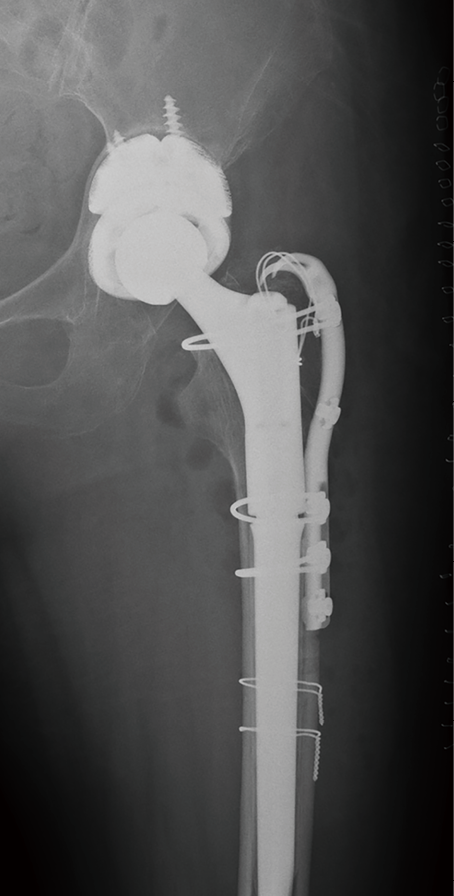

病例2:髋关节置换术后严重髋臼内陷, 使用3D打印垫块及组配柄完美重建